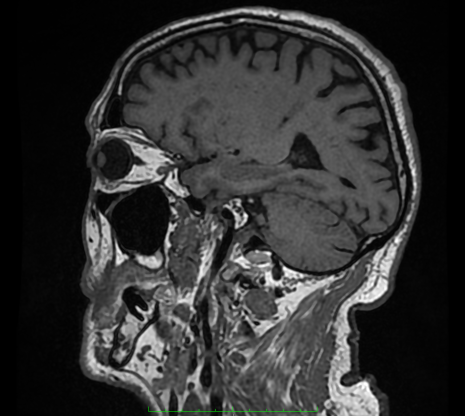

Теперь представьте себе, что атомы водорода — это струны гитары, которые натянуты тем больше, чем сильнее магнитное поле. Атомы водорода в разных местах головы становятся по-разному «натянутыми”. Там, где водорода нет, там нет и струны с натяжением такой силы. Представьте, будто так же, как вы поете гитаре, аппарат поет этим струнам разные звуки. Затем аппарат слушает, запела ли какая-нибудь струна в ответ. Там, где струны ответили, на соответствующую точку карты магнитного поля ставится белая точка (есть резонирующие атомы водорода), там, где не ответили ставится черная точка (нет атомов водорода). Вот так выглядит в конечном итоге картинка (рис. 3).

Рис. 3. Магнитно-резонансно томографический снимок головы